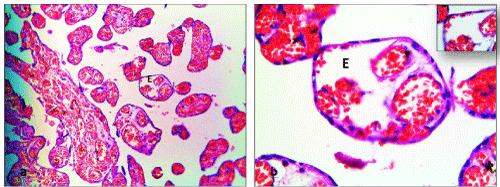

| Figure 3: Photomicrographs of diabetic group of placenta showing; a) A fullterm placenta includes sections of many villus stems (V), containing edema (E), (H&E 10X . b) At higher magnification, the villus connective tissue denoting edema (E), (H&E 40X).Inset |